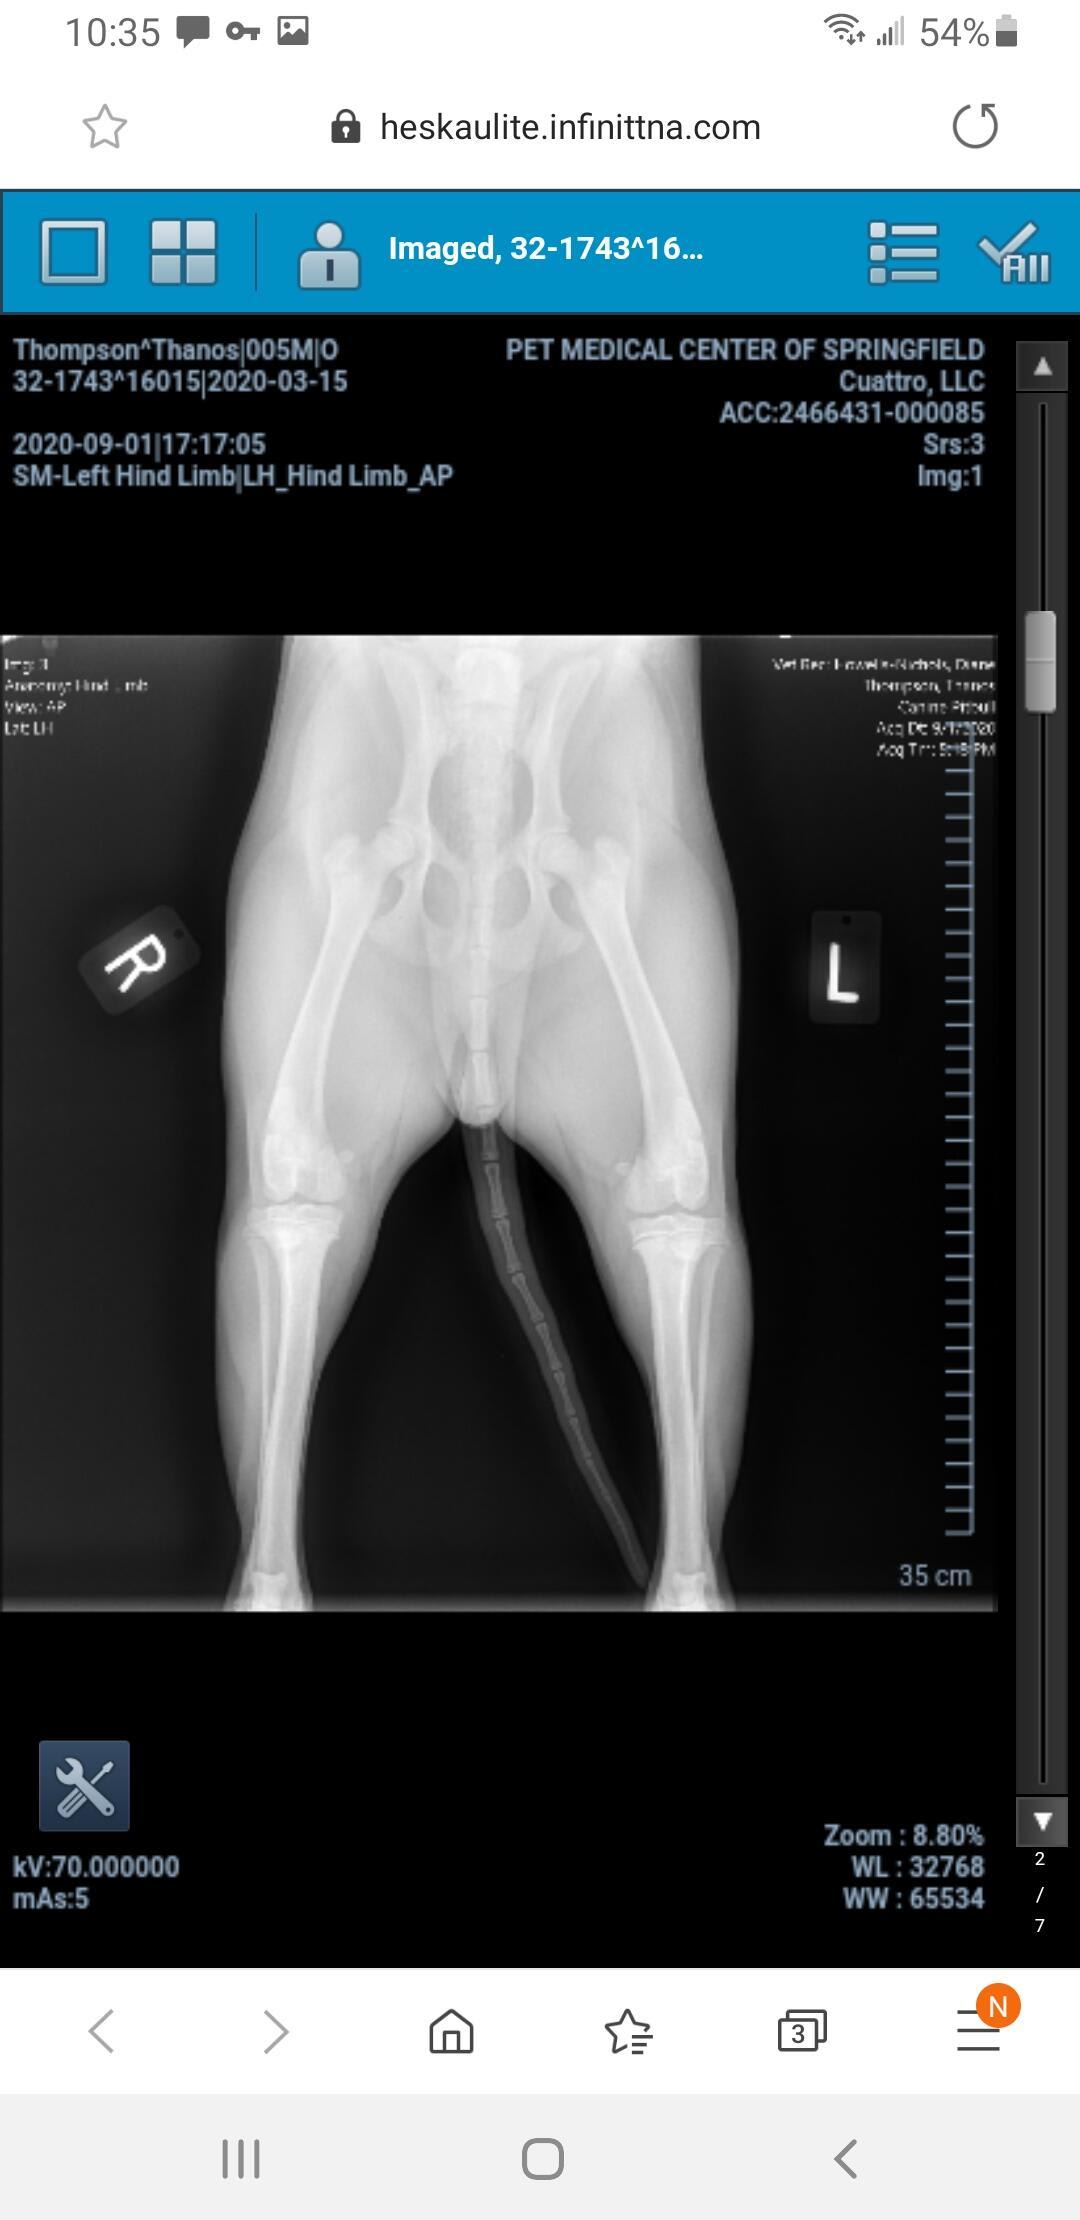

My dog jumped for a water bottle and landed wrong. Is he injured?

Pet's info: Dog | American Pit Bull Terrier | Male | unneutered | 5 months and 18 days old | 37 lbs

Dog jumped up for water bottle and landed wrong

Hello. Most likely your veterinarian recommended surgery to repair the fracture, & I would confirm that that is the best way to go. So sorry this has happened to Thanos, but glad you are looking out for him. Thanks for contacting Petco Pet Education Center, formerly Petcoach.